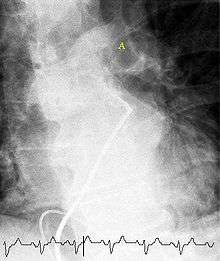

Selective pulmonary angiogram revealing clot (labeled A) causing a central obstruction in the left main pulmonary artery. ECG tracing shown at bottom.

CT pulmonary angiography is the recommended first line diagnostic imaging test in most people.[43] Historically, the gold standard for diagnosis was pulmonary angiography, but this has fallen into disuse with the increased availability of non-invasive techniques. Ultrasound of the legs can confirm the presence of a PE but cannot rule it out.[44]